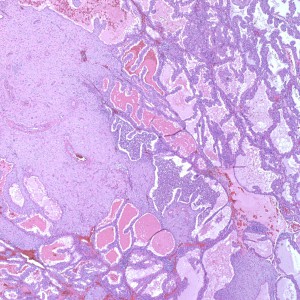

The biopsy contains rare areas like this with scan strips of surface tubal and lower uterine segment epithelium, but without any real appreciable glandular tissue.

However, in one field we see a well-circumscribed nodule that, on low power, is very pink and glassy appearing, with large cells admixed.